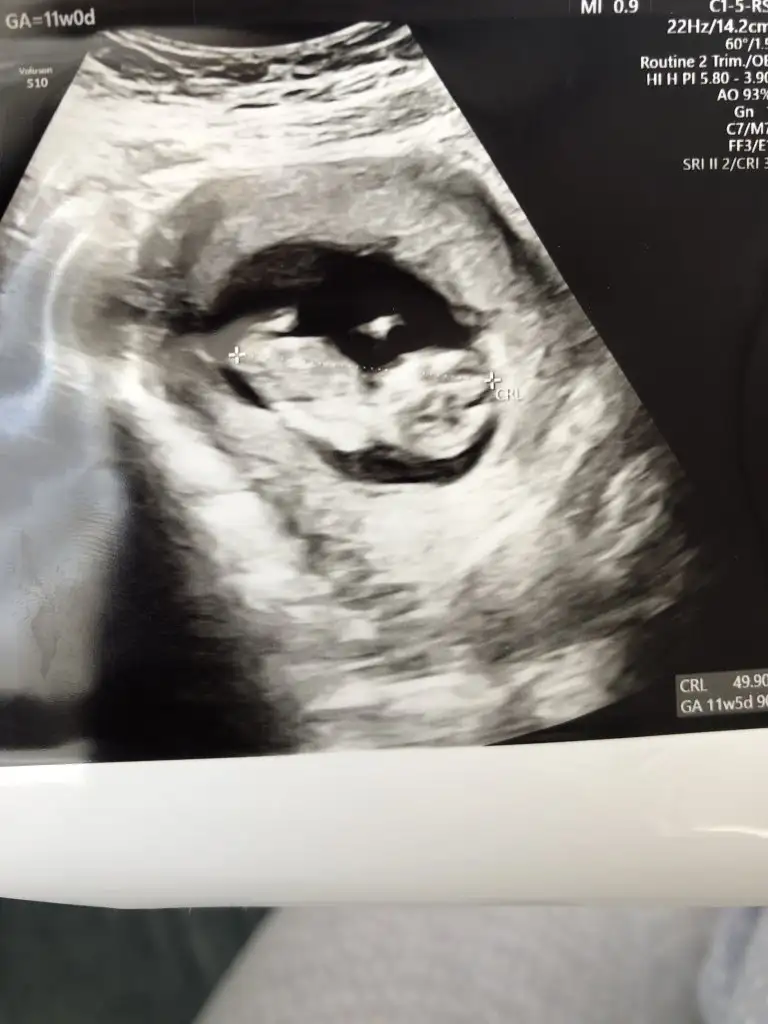

Ben bugün gene kontroldeydim Ikra meyra her seferin farklı tahminde bulunuyor ama bugün met ve emin söyledi. Bakalım sen ne diyeceksin? Bemce poposu dönük ama öyle bişey demedi.

Eklentiler

• 75A4491F-6DB9-4A8B-8E02-02864430ECE0.webp

13 KB · Görüntüleme: 79

• 4823C446-5F34-47E2-917C-5CA695CA87DF.webp

24,3 KB · Görüntüleme: 67

• E969A068-7C17-45EB-ACF3-EBD5B5F8B5D2.webp

23,8 KB · Görüntüleme: 76

Kız gibi sanki daha önceki karanlık USG emin olmamıştım